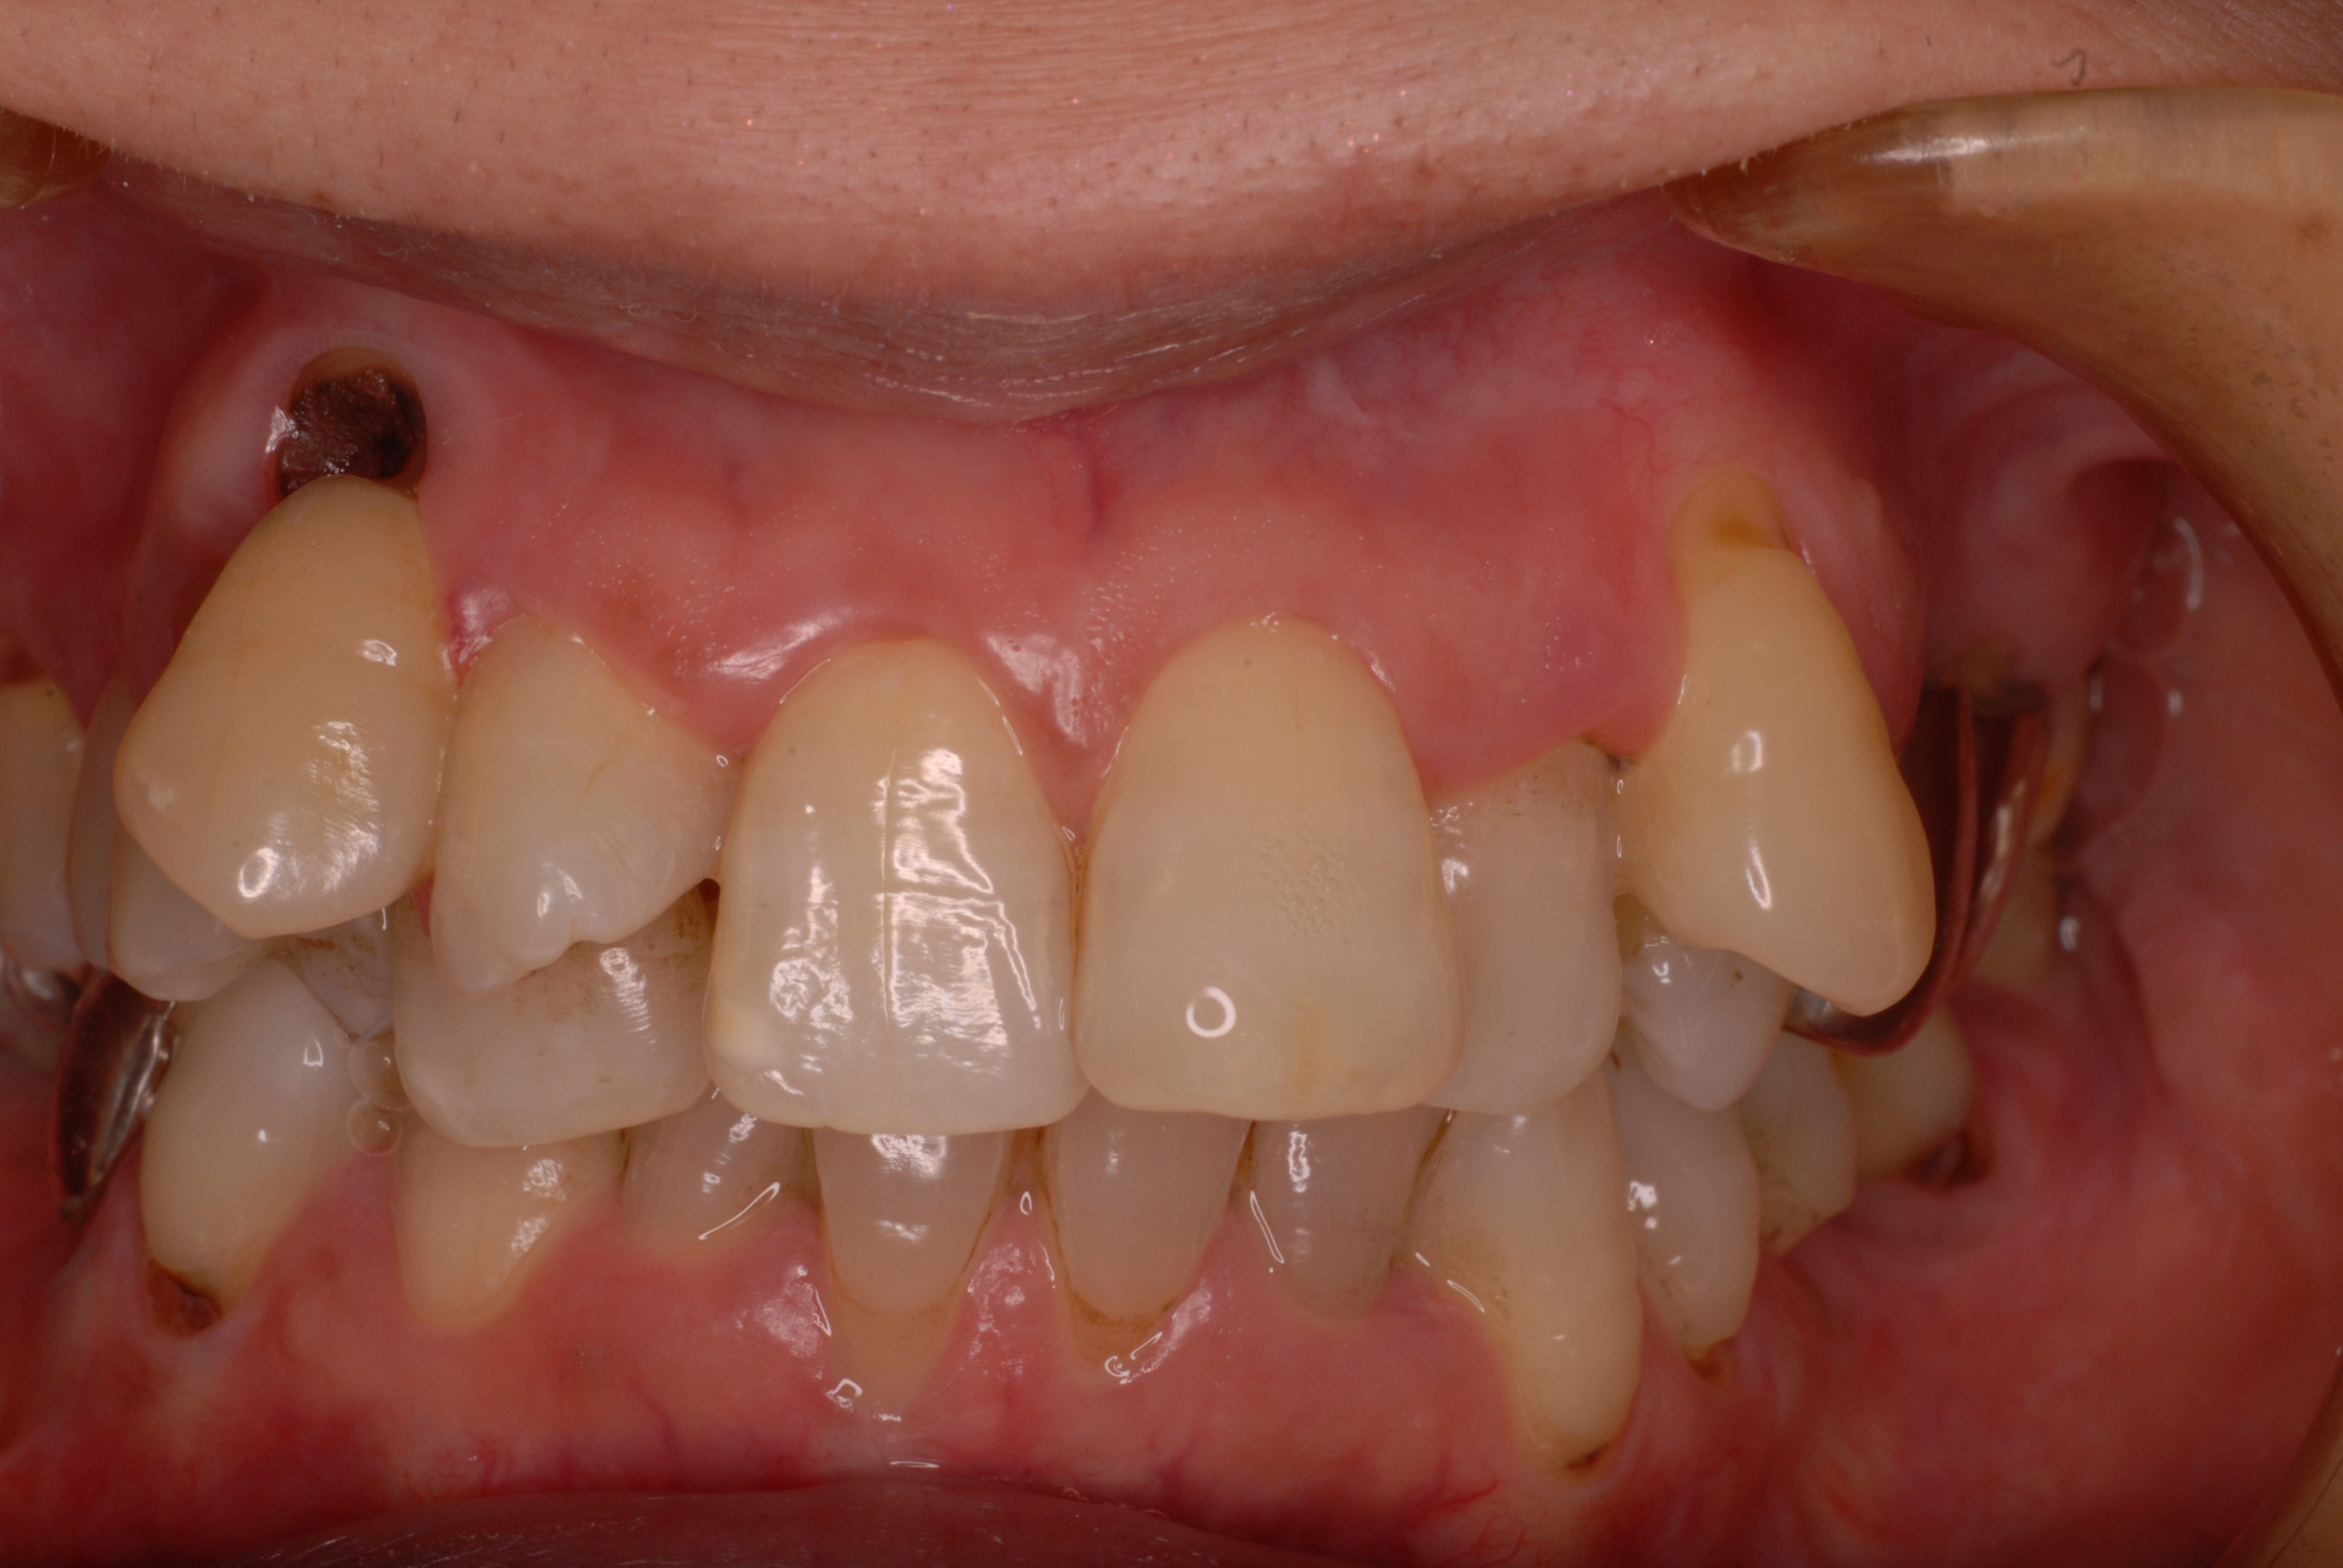

下の写真の方は虫歯と歯の間の歯周病が酷かったのです。

虫歯の治療も完全にできませんし、歯の位置が悪く又重なっている為に歯周病が治らずに説得に数カ月を有した後に矯正することになりました。

写真左の歯のうち過剰歯と糸きり歯の隣を抜きました。